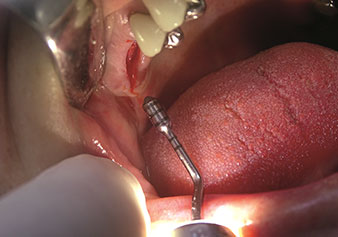

Internal sinus lift

W&H also offers the perfect solution for the internal sinus lift.

Following preparation of the maxillary sinuses with the corresponding instrument set (Fig. 3), the new Z35P instrument (Fig. 4) is used to lift the membrane hydrodynamically. The same instrument set can also be used for piezosurgical preparation of the implant bed in increasing diameters (Figures 3 and 4 included with the kind permission of Dr Mario Kirste, Frankfurt/Oder).

Preparation of maxillary sinus floor and lifting of Schneiderian membrane (Z35P instrument)

Fig. 4: Preparation of maxillary sinus floor and lifting of Schneiderian membrane (Z35P instrument). Photo: © Dr Mario Kirste (Frankfurt / Oder)